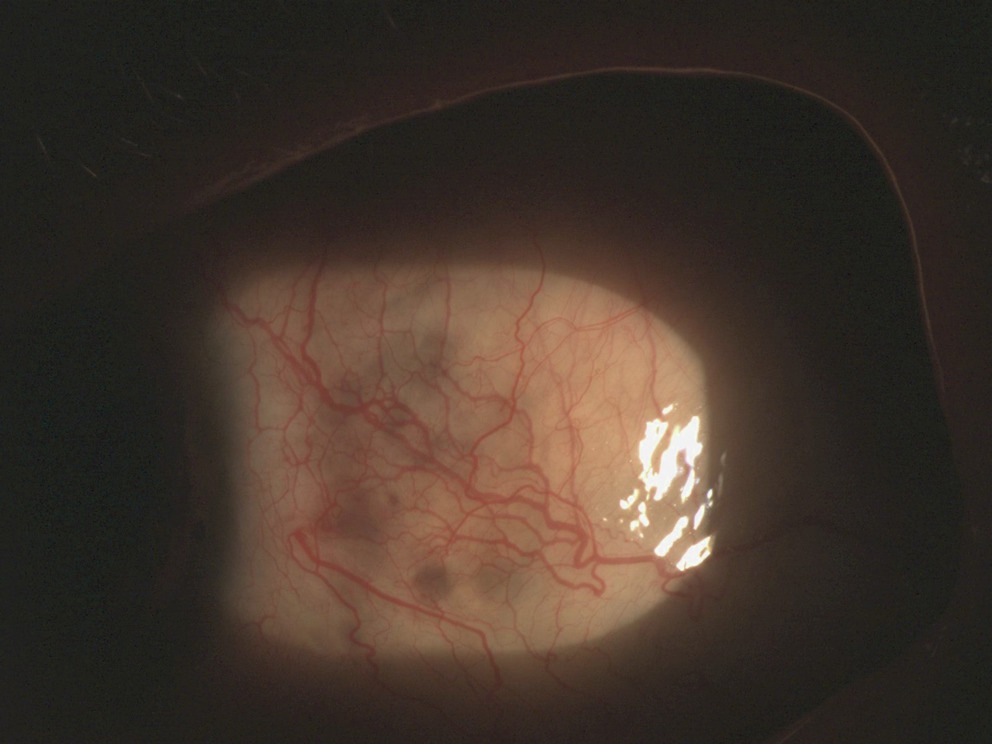

fig. 33-6,

Fig. 33-6

Stade séquellaire d'une kératite post-zostérienne avec aspect de néovaisseaux et dépôts lipidiques.